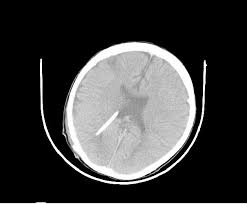

Postoperative Ct Scan Of The Patient Axial View Showing Placement Of Download Scientific Diagram